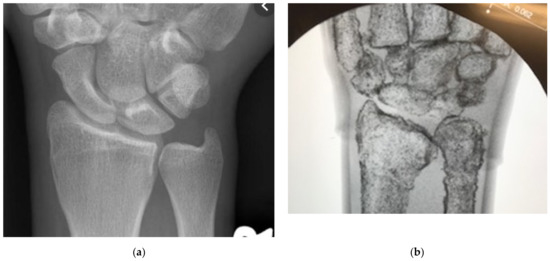

Rather than change the material composition of the phantom, which would require us to remake portions of the model from the ground up with more expensive components, we chose to leverage the behavior of X-rays and metal to create artificial feedback. We settled on the low-cost option of mixed iron powder with the latex periosteum to raise the apparent density of the material. As the high-density iron would be localized to the bone surface, it would create interference with the X-rays, allowing us to overcome the lack of inherent density in our materials. We mixed batches of latex and iron by increasing the weight fraction of the iron by 5% and then tested them under fluoroscopy to gauge the ease with which constitutive features were shown when compared to live tissues. This comparison is shown statically with fluoroscopic images of a human wrist in Figure 10a and our DRF phantom in Figure 10b. The two provide sufficiently distinct imaging responses while providing the same tactile feedback to differentiate hard and soft tissue features. “On average 40%/weight of iron filings” in four layers of latex was sufficient to visualize the phantom bones [1]. The iron required for a single phantom is under 10 g, an essentially negligible cost. The iron-laden latex maintains the same curing time and conditions, and surgical feedback indicated no differentiation to the tactile response of the overall model. Slight changes, if any, to performance are likely overshadowed by the ballistic gelatin-bulk tissue behavior. Manipulating the fracture while imaging, as shown in Figure 11, allows residents to pair tactile and visual stimuli to create a more holistic understanding of the procedure [1,6,8,9,20,21].

Figure 10.

(a) Human hand under fluoroscopy to show hard and soft tissue feedback. (b) Our DRF phantom under fluoroscopy demonstrating differentiable hard and soft replica tissues [1].